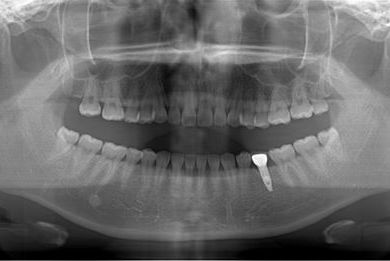

インプラントの症例写真 IMPLANT

インプラント治療

| 性別/年齢 | 女性 / 29歳 | ||||||||||||||||||||||||||||||||

| 主訴 | インプラント治療と、親知らずの抜歯の相談。なるべく安価で、短期間で終了して欲しい。 | ||||||||||||||||||||||||||||||||

| 治療方針 | 欠損部分をインプラント治療にて、機能的・審美的回復を行う。 | ||||||||||||||||||||||||||||||||

| 治療内容 | インプラント1本、メタルボンドセラミッククラウン1本 | ||||||||||||||||||||||||||||||||

| 総治療費 | 252,000円 | ||||||||||||||||||||||||||||||||

| 治療期間 | 11ヶ月 |